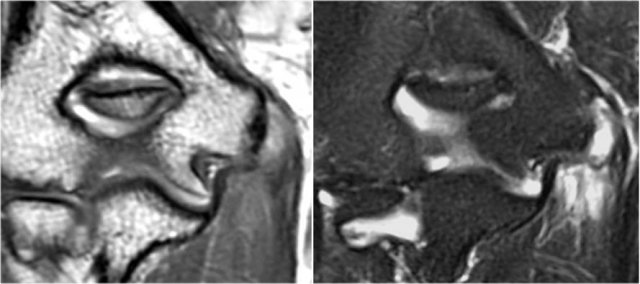

The findings on the coronal MR-images are quite uncommon.

If you would see this in the capitellum you would call it an osteochondral lesion of the capitellum.

So this is called an osteochondral lesion of the trochlea.

Notice the small cystic changes (white arrow).

There is also a small cartilage defect.

An osteochondral lesion of the trochlea is usually seen in younger patients, who have an immature skeleton.

It is seen in the lateral trochlea like in this case due to repetitive hyperextension in an area with tenuous blood supply.

It is also seen in the medial trochlea due to laxity and posteromedial abutment.

Here a different patient.

Notice that it is a young patient, because the physis is still open.

There is a large osteochondral lesion in the lateral trochlea (yellow arrows).

Notice the edema in the subchondral bone (red arrow).

The cartilage is still intact.